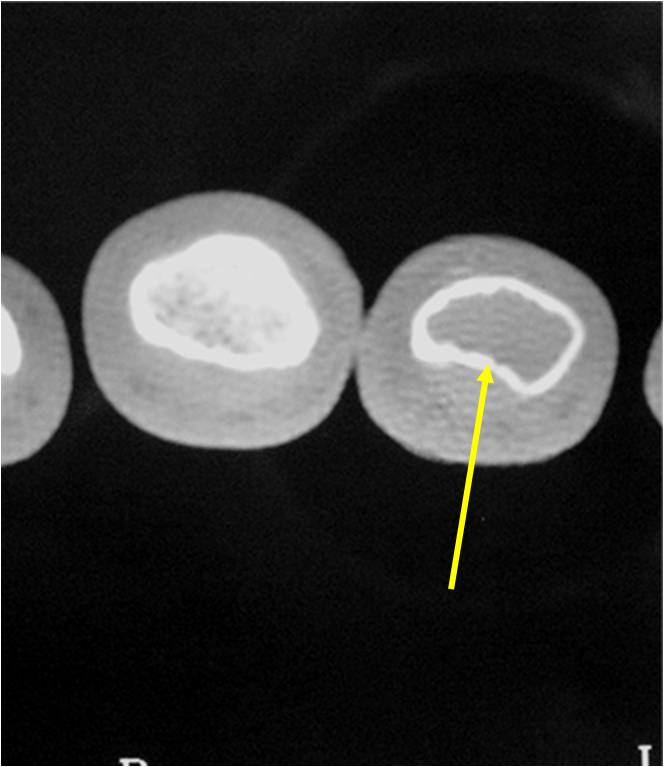

- Endosteal erosion>2/3 cortical thickness on a CT scan

- There should never be any cortical destruction nor a soft tissue component. If this exists then the tumor must be a chondrosarcoma.

- Endosteal scalloping and cortical expansion is acceptable for phalangeal tumors. In most benign long bone cartilage tumors there is minimal endosteal scalloping but there should be no cortical expansion nor thickening. There should be no cortical destruction and no soft tissue component associated with an enchondroma. Cortical destruction, periosteal thickening, cortical expansion and a soft tissue component indicates a chondrosarcoma of the long bone.